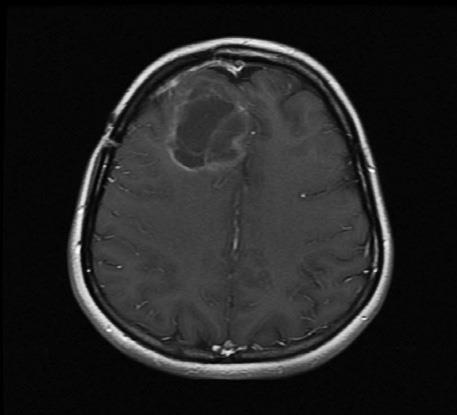

Энцефалограммы 20-летнего студента, которого лечат модифицированным вирусом полиомиелита (PVS-RIPO), вводимым через катетер, подсоединенный прямо к опухоли.

Слева – опухоль до лечения (затененная область в верхней левой части мозга). В середине – опухоль после двух месяцев лечения (она кажется даже больше из-за воспаления, вызванного иммунным ответом). Справа – опухоль, уменьшившаяся после девяти месяцев лечения.